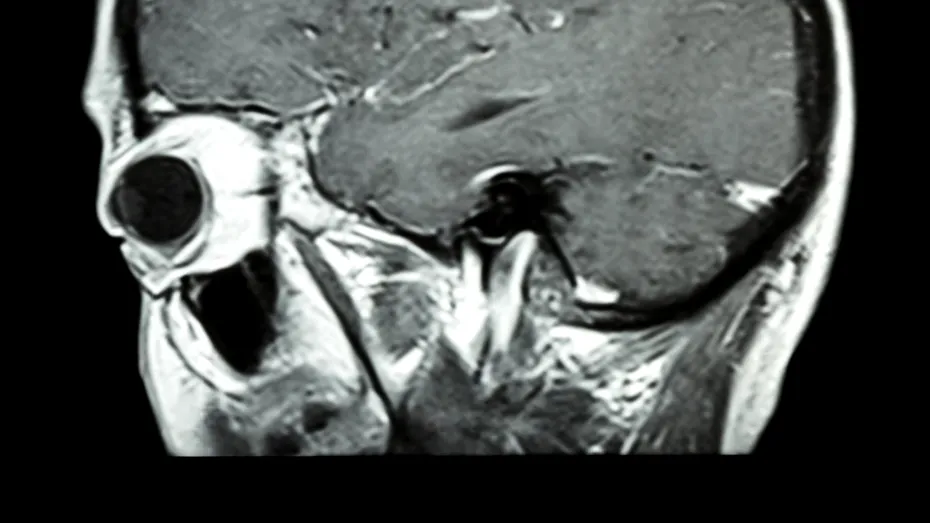

„Sunt un caz rar. Am supravieţuit cancerului cerebral, mi-am revenit după ce am experimentat boala psihică şi pot să descriu ce mi s-a întâmplat. Dacă ar fi să-i ascultăm pe psihiatri şi neurologi – specialiştii în materie de creier şi sistem nervos – este de-a dreptul neobişnuit ca cineva cu un asemenea grad de afectare să poată fi tratat cu succes şi să se întoarcă din lumea întunecoasă a bolnavilor din această categorie”, mărturiseşte Barbara K. Lipska la începutul cărţii sale.

În cartea „Nebunie şi vindecare”, Barbara rememorează încercările prin care a trecut după ce a fost diagnosticată cu cancer cerebral şi cum cele mai simple lucruri cum ar fi pregătirea cinei, drumul până acasă sau folosirea centurii de siguranţă au devenit imposibil de pus în practică. Cercetătoarea atrage atenţia tocmai asupra faptului că schimbările de comportament pot indica probleme grave.

„Dacă cineva iubit sau un coleg de muncă alunecă la un moment dat şi rămâne paralizat pe o parte a corpului, cei mai mulţi dintre noi ar recunoaşte simptomele unui atac cerebral şi ar suna imediat la 112. Simptomele acute, ca acestea, sunt uşor de remarcat. Dar schimbările comportamentale pot fi mult mai greu de recunoscut şi acceptat ca semnale de alarmă sau probleme serioase”, precizează ea. „Schimbările comportamentului obişnuit semnalează, de cele mai multe ori, faptul că în interiorul creierului unei persoane se întâmplă ceva ce nu trebuie ignorat. Ieşirile mele emoţionale exagerate – furia, suspiciunea, nerăbdarea – sugerau că lobul frontal trece prin schimbări catastrofale”, mai spune ea.

„Creierul are o capacitate remarcabilă de autovindecare după diferite tipuri de răni şi atacuri, o proprietate care-i uimeşte pe cercetători şi pe oamenii de ştiinţă. Chiar şi pacienţii cu leziuni cerebrale severe se pot recupera câteodată aproape în întregime. Dar, până acum, sincer vorbind, capacitatea creierului de a se autovindeca este pur şi simplu miraculoasă”, recunoaşte Barbara în cartea sa.